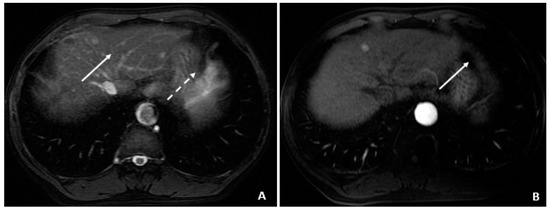

A 50-year-old male was diagnosed with CHB at age 40. With lamivudine treatment for 3 years, he achieved HbsAg seroconversion to anti-HBs and lamivudine was discontinued. Table 4 outlines his course. Five years later, on a follow up examination he was found to have HBV DNA 847 copies/mL, ALT 33 IU/L, and AFP 20.5 ng/mL. An MRI (December 2009) showed a 5 cm lesion consistent with HCC (Figure 1A,B). Repeat AFP was 17.8 ng/mL at time of HCC diagnosis, and AFP-L3% was 75.6. He underwent transarterial chemoembolization (TACE) with successful resolution (Figure 2A,B) and restarted lamivudine. The AFP remained at 3.0 ng/mL, and the MRI showed no evidence of HCC the following year. Two years after initial treatment, the AFP increased to 5.9 ng/mL with 57.5% L3. The MRI next month showed recurrent HCC at the treated site (Figure 3). The patient underwent laparoscopic radiofrequency ablation and therasphere treatment.

Figure 3.

Recurrent HCC 2 Years Later (April 2011). (A) The contrast-enhanced CT image shows a hyperenhancing lesion in the left lobe (arrows) with adjacent tumor thrombus within the portal vein (dashed arrow). (B) The subsequent axial T1-weighted fat-suppressed postcontrast MRI image shows the lesion (arrows) to a slightly better advantage, along with the portal vein tumor thrombus (dashed arrow). (C) The diffusion-weighted image shows marked hyperintensity (arrow) within the left lobar mass, corresponding to diffusion restriction, typical of malignant tumors.

Subsequent %L3 AFPs remained persistently high with minimally elevated total AFP levels, which indicated recurrent/progressive HCC.